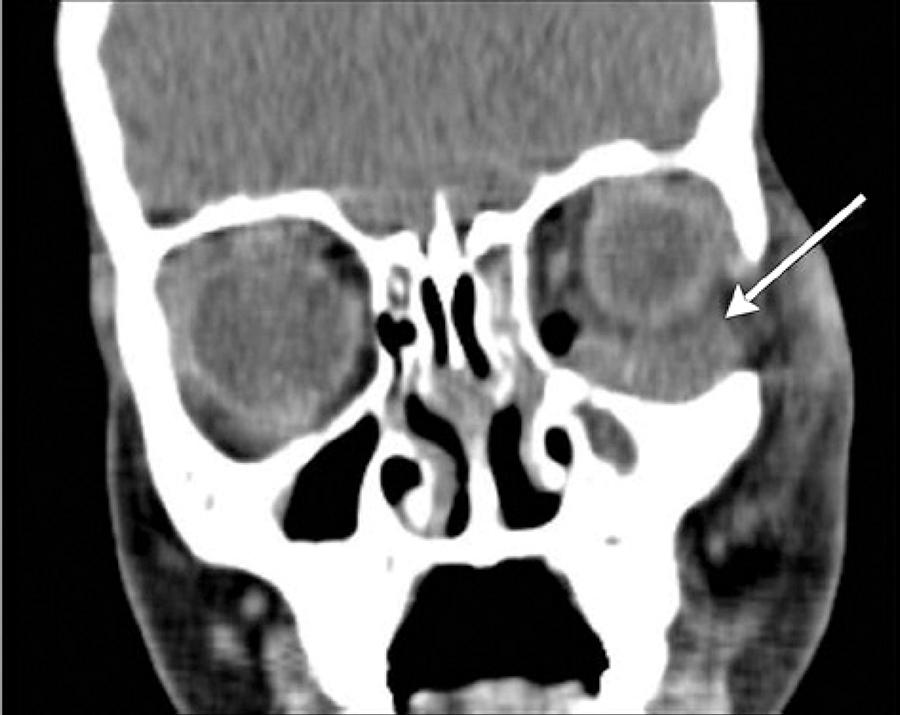

Fifty-one patients met the criteria for the study and had available medical records (29 male, 22 female). Thirty patients were treated on the otorhinolaryngology service and twenty-one patients were treated on the opthalmology service. The age range was 1 to 63 years (mean, 19.92 ± 17.98). Approximately 70% patients (n=36) were younger than 18 years of age. Thirty-two (62.7%) were diagnosed with preseptal cellulitis and 19 (37.3%) were diagnosed with postseptal cellulitis. After detailed evaluations, 15 were diagnosed with a subperiosteal abscess (SPA) and 4 with orbital cellulitis. No one had an intraorbital abscess or a cavernous sinus thrombosis. The age and gender was similar for the two groups. SPA was localized as medial (n=8) (Figure 1), superiomedial (n=4) (Figure 2), inferior (n=1) (Figure 3), and inferiomedial (n=1) (Figure 4). In the postseptal cellulitis group, bilateral pansinusitis was found in 5, unilateral pansinusitis in 6, unilateral maxillary, ethmoid, and frontal sinusitis in 5, unilateral maxillary and ethmoid sinusitis in 2, and unilateral maxillary sinusitis in 1. In the preseptal cellulitis group, bilateral pansinusitis was present in 9, unilateral pansinusitis in 10, unilateral maxillary, ethmoid, and frontal sinusitis in 4, unilateral maxillary, ethmoid sinusitis in 5, and unilateral ethmoid sinusitis in 4 patients. Five patients with medial SPA were treated with endoscopic sinus surgery, one patient with inferior SPA was treated with external surgery, and six patients with other localizations were treated with combination of endoscopic sinus surgery and external surgery. The seasonal distribution of this pathology is shown in figure 5.

Historically, the classic external approach for SPA is the external ethmoidectomy via a Lynch incision(29). In 1993, Manning reported drainage via an intranasal, endoscopic approach(13). Since then, many studies have confirmed the endoscopic approach as the most used method for the management of SPA(29). In medial or medial-inferior SPA, a transnasal endoscopic approach is possible, but in superior orbital abscess an external incision is required(3). In our study, five patients with medial SPAs were treated with endoscopic sinus surgery, one patient with an inferior SPA was treated with external surgery, and six patients with other localizations were treated with a combination of endoscopic sinus surgery and external surgery.